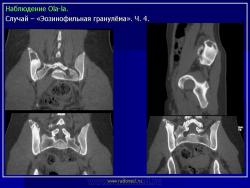

Тело позвонка является наиболее часто поражающейся частью позвоночника. Ранние поражения проявляются, как литические очаги.

Формируется «VERTEBRA PLANA», что может привести к боли и значительным неврологическим расстройствам.

LCH у 17-летней девочки с болями в спине.

На КТ изображении визуализируется неправильной формы литическая деструкция тела позвонка (стрелка).

Равномерный распад тела позвонка (белая стрелка), с образованием «VERTEBRA PLANA», межпозвонковые диски сохранены (наконечники стрел).

Литические поражения ребер (черные стрелки).